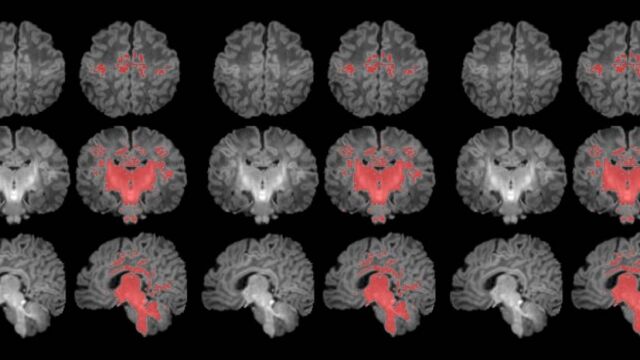

Resonancia magnética en el primer mes de vida

Para llevar a cabo el estudio se reclutó a mujeres embarazadas en seguimiento en el Hospital Clínic Barcelona, el Hospital de Sant Pau y el Hospital Sant Joan de Déu. Se monitorizaron los niveles de contaminantes atmosféricos a los cuales estaban expuestos durante la gestación y, después del parto, se seleccionó a 132 recién nacidos. A estos se les realizó una resonancia magnética antes de cumplir el primer mes de vida para observar el grado de maduración cerebral según sus niveles de mielinización.

Los resultados muestran una correlación clara entre una mayor exposición materna a PM2.5 durante el embarazo y una menor mielinización en el cerebro de los recién nacidos.